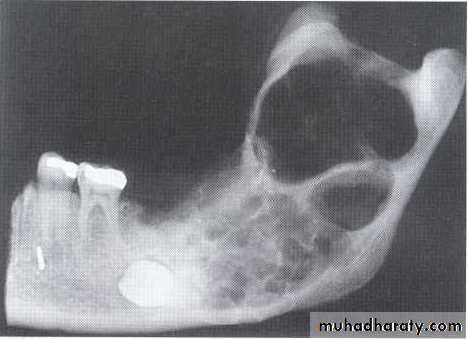

•Large multilocular aneurysmal bone cyst

in the ramus with marked expansion and

the displacement of/8.

5-year-old boy showing the typical bilateral multilocular lesions of

cherubism affecting the mandible (arrowed).Multiple but separate radiolucent lesions